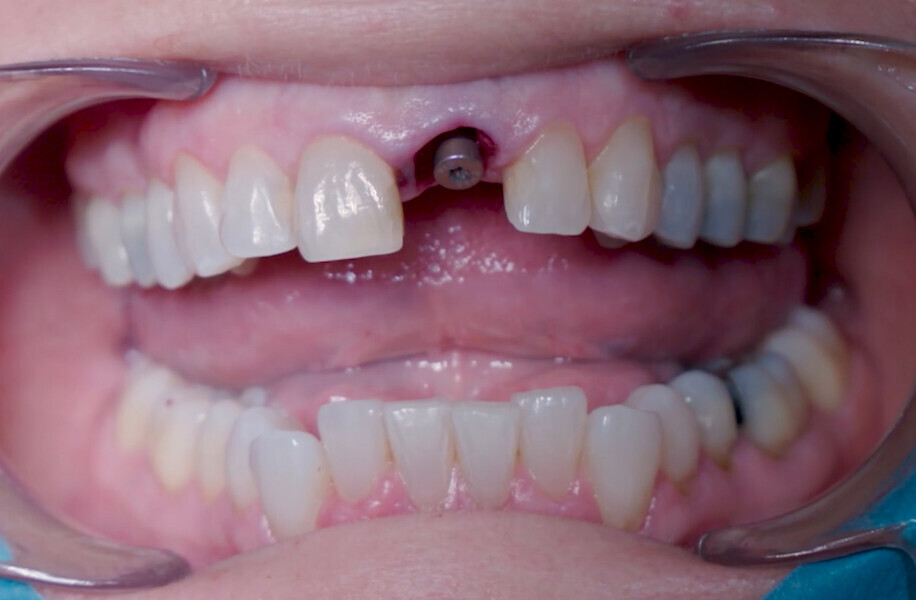

Fig. 11: Final implant position assessment.

Fig. 12: Final implant position assessment in relation to gingival margins.